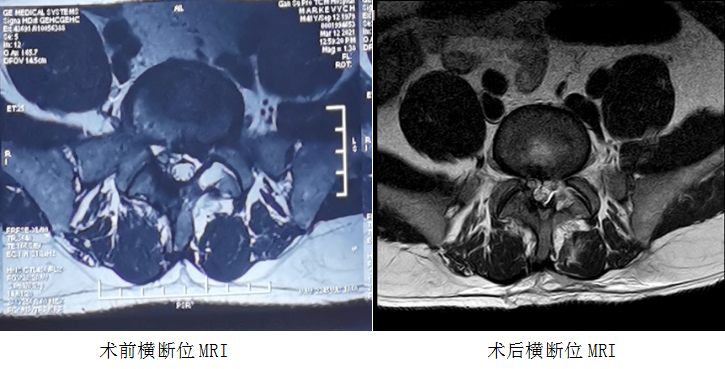

患者男性,41岁,系兰州交通大学乌克兰籍在读博士,因“腰痛伴左下肢疼痛、麻木1月余,加重1周”收住。该患者1月前出现腰痛伴左下肢疼痛、麻木症状,经针灸、理疗、口服药物等保守治疗后,疼痛未见缓解。1周前,症状加重,不能行走。病痛给他的日常生活和工作造成了极大的困扰,几经辗转,来到我院门诊就诊。进行了细致地查体后,明确诊断:1.腰椎间盘突出伴有神经根病(L5/S1,左侧);2.腰椎间盘突出症术后(L4/5);3.椎体终板炎(L5/S1)。结合病史临床表现及影像学检查,经与患者及家属充分沟通后收住入院。经完善相关检查后,于4月8日下午行全麻经皮脊柱内镜下经椎板间入路髓核摘除神经根减压术(L5/S1,左侧),术后患者腰痛及左下肢疼痛消失,平卧6小时后,患者配戴腰围下地活动,无特殊不适,患者对手术疗效非常满意。

术前MRI